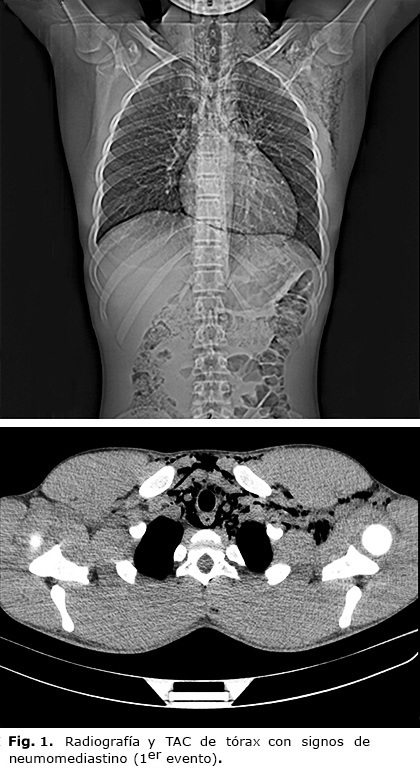

Fue valorado en conjunto con cirugía, se indicó radiografía de tórax que muestra signos sugestivos de neumomediastino y enfisema subcutáneo. Se realizó Tomografía Axial Computarizada (TAC) de tórax, que informa la presencia de aire en tejido celular subcutáneo que se extiende desde el cuello, región anterior del tórax, región axilar izquierda y ligeramente hacia los planos posteriores izquierdos. Neumomediastino que decola mediastino en todos sus compartimentos y se extiende hasta ramas secundarias de la arteria pulmonar izquierda (Fig. 1).